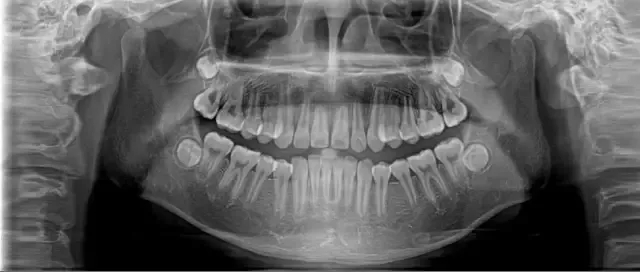

主要用于检查、分析、判断病情,帮助医生及时、正确的诊断,进而指导治疗工作。通常呈现:全口牙齿、牙周、牙槽骨、颅骨、颌骨、上颌窦、鼻腔、双侧颞颌关节、下颌神经管等形态、位置、软组织侧貌等图像。

也就是说,医生可通过全景片可观察到牙齿健康状况:是否有隐形龋齿、埋伏阻生牙、多生牙、牙槽骨吸收、牙龈萎缩、口腔内是否长有瘤体等,更好地为患者设计治疗方案。